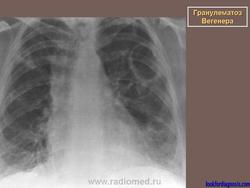

Вегенера гранулематоз

Поражение легкихразвивается у 3/4 больных, проявляется формированием инфильтратов, которые могут распадаться и образовывать полости. Иногда наблюдается плеврит.

Рентгенологическое исследование легких: инфильтраты, часто с распадом и образованием полостей, редко - плеврит.